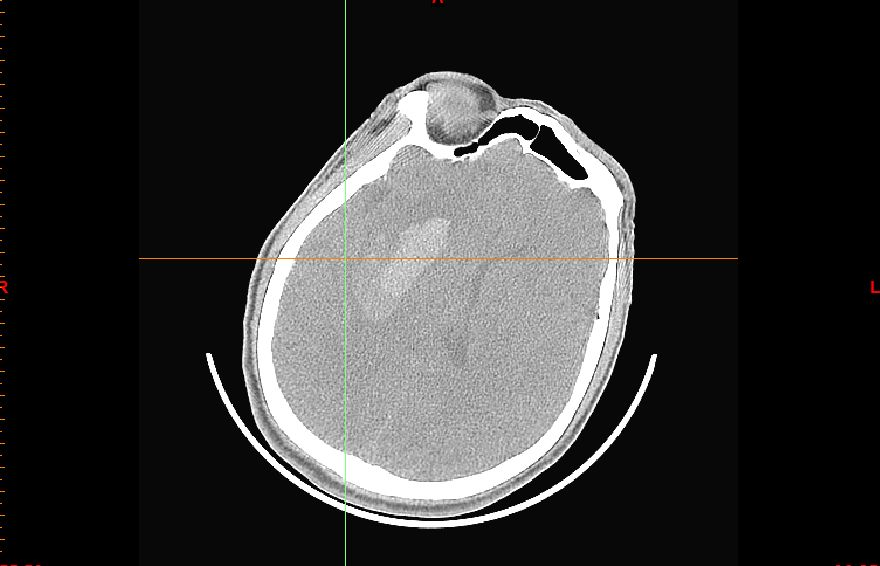

仔细观察CT片可见血肿呈分层现象

再仔细观察并划定血肿分层区域,可设定血肿为高密度区域、低密度区域,和正常脑组织对比

以红色区域划分为高密度区域、蓝色区域划分为低密度区域

测量各密度区域CT阈值,可见高密度区域(红色区域)CT阈值为60.66,低密度区域(蓝色区域)CT阈值为44.39,正常脑组织区域CT阈值为20.94。